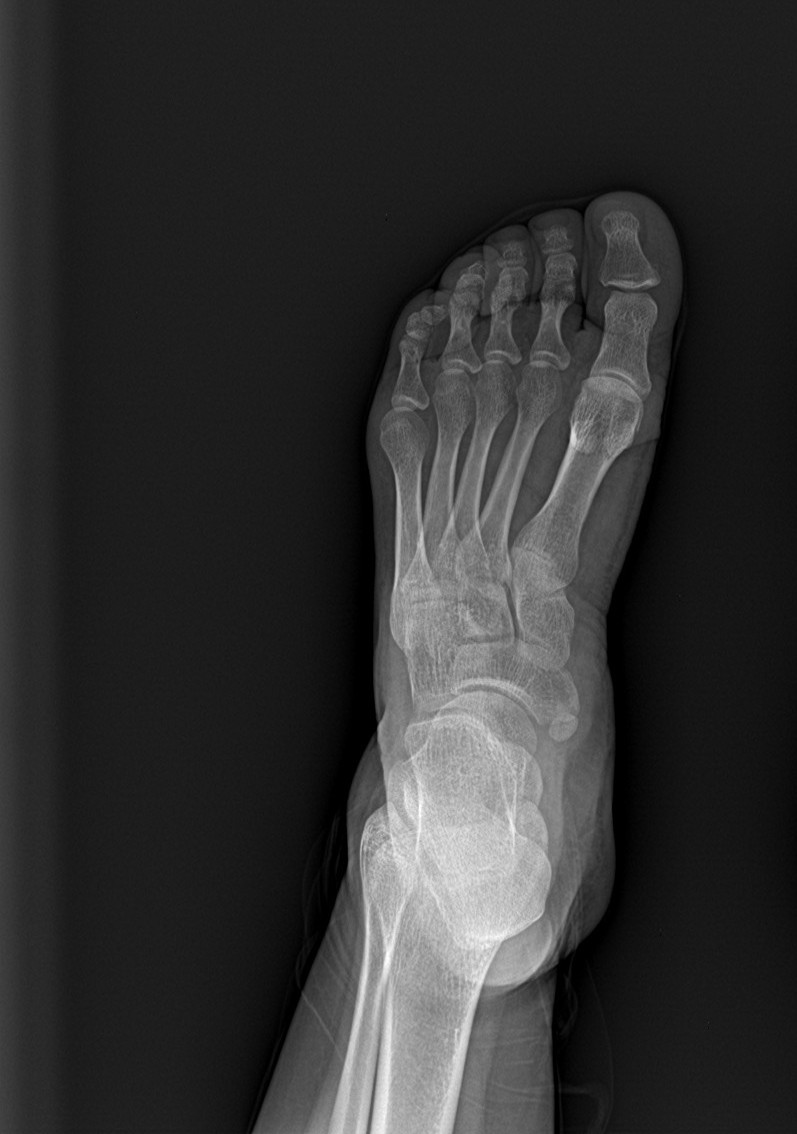

AP